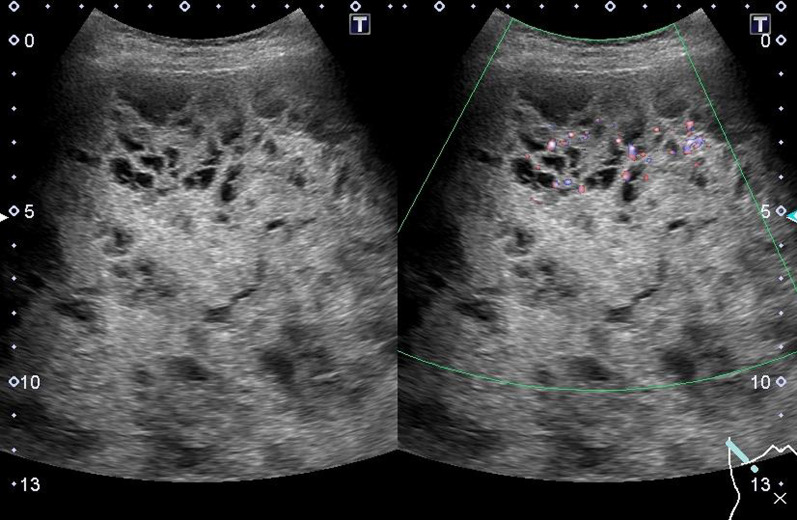

Fig. 1.

Abdominal ultrasonography. The inside of the tumor was recognized as a structure divided into many spaces, and blood flow was confirmed in the septum